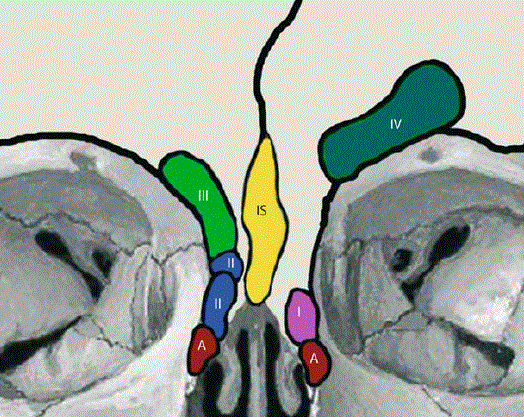

La sinusotomie frontale Draf III

Il s’agit de l’intervention la plus technique par voie endonasale. Elle consiste à fraiser le plancher des deux sinus frontaux et à les réunir en fraisant la cloison qui les sépare. Elle nécessite un temps de cicatrisation important après la chirurgie et des lavages de fosse nasales réguliers.